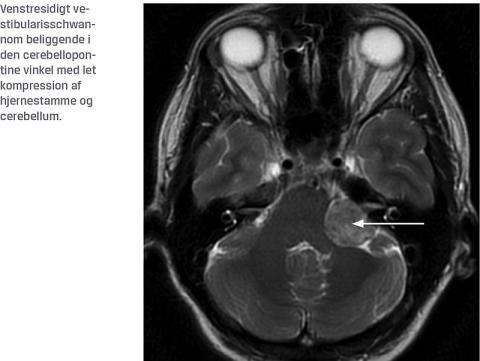

Vestibularisschwannomer (VS) er godartede intrakraniale tumorer, der udgår fra de schwannske celler, der omskeder den ottende kranienerve i den cerebellopontine vinkel. Denne tumor blev tidligere benævnt acusticusneurinom, men det har vist sig, at det histologisk ikke drejer sig om et neurinom, og at tumoren ikke udspringer fra nervus cochlearis/acusticus, men derimod fra n. vestibularis.